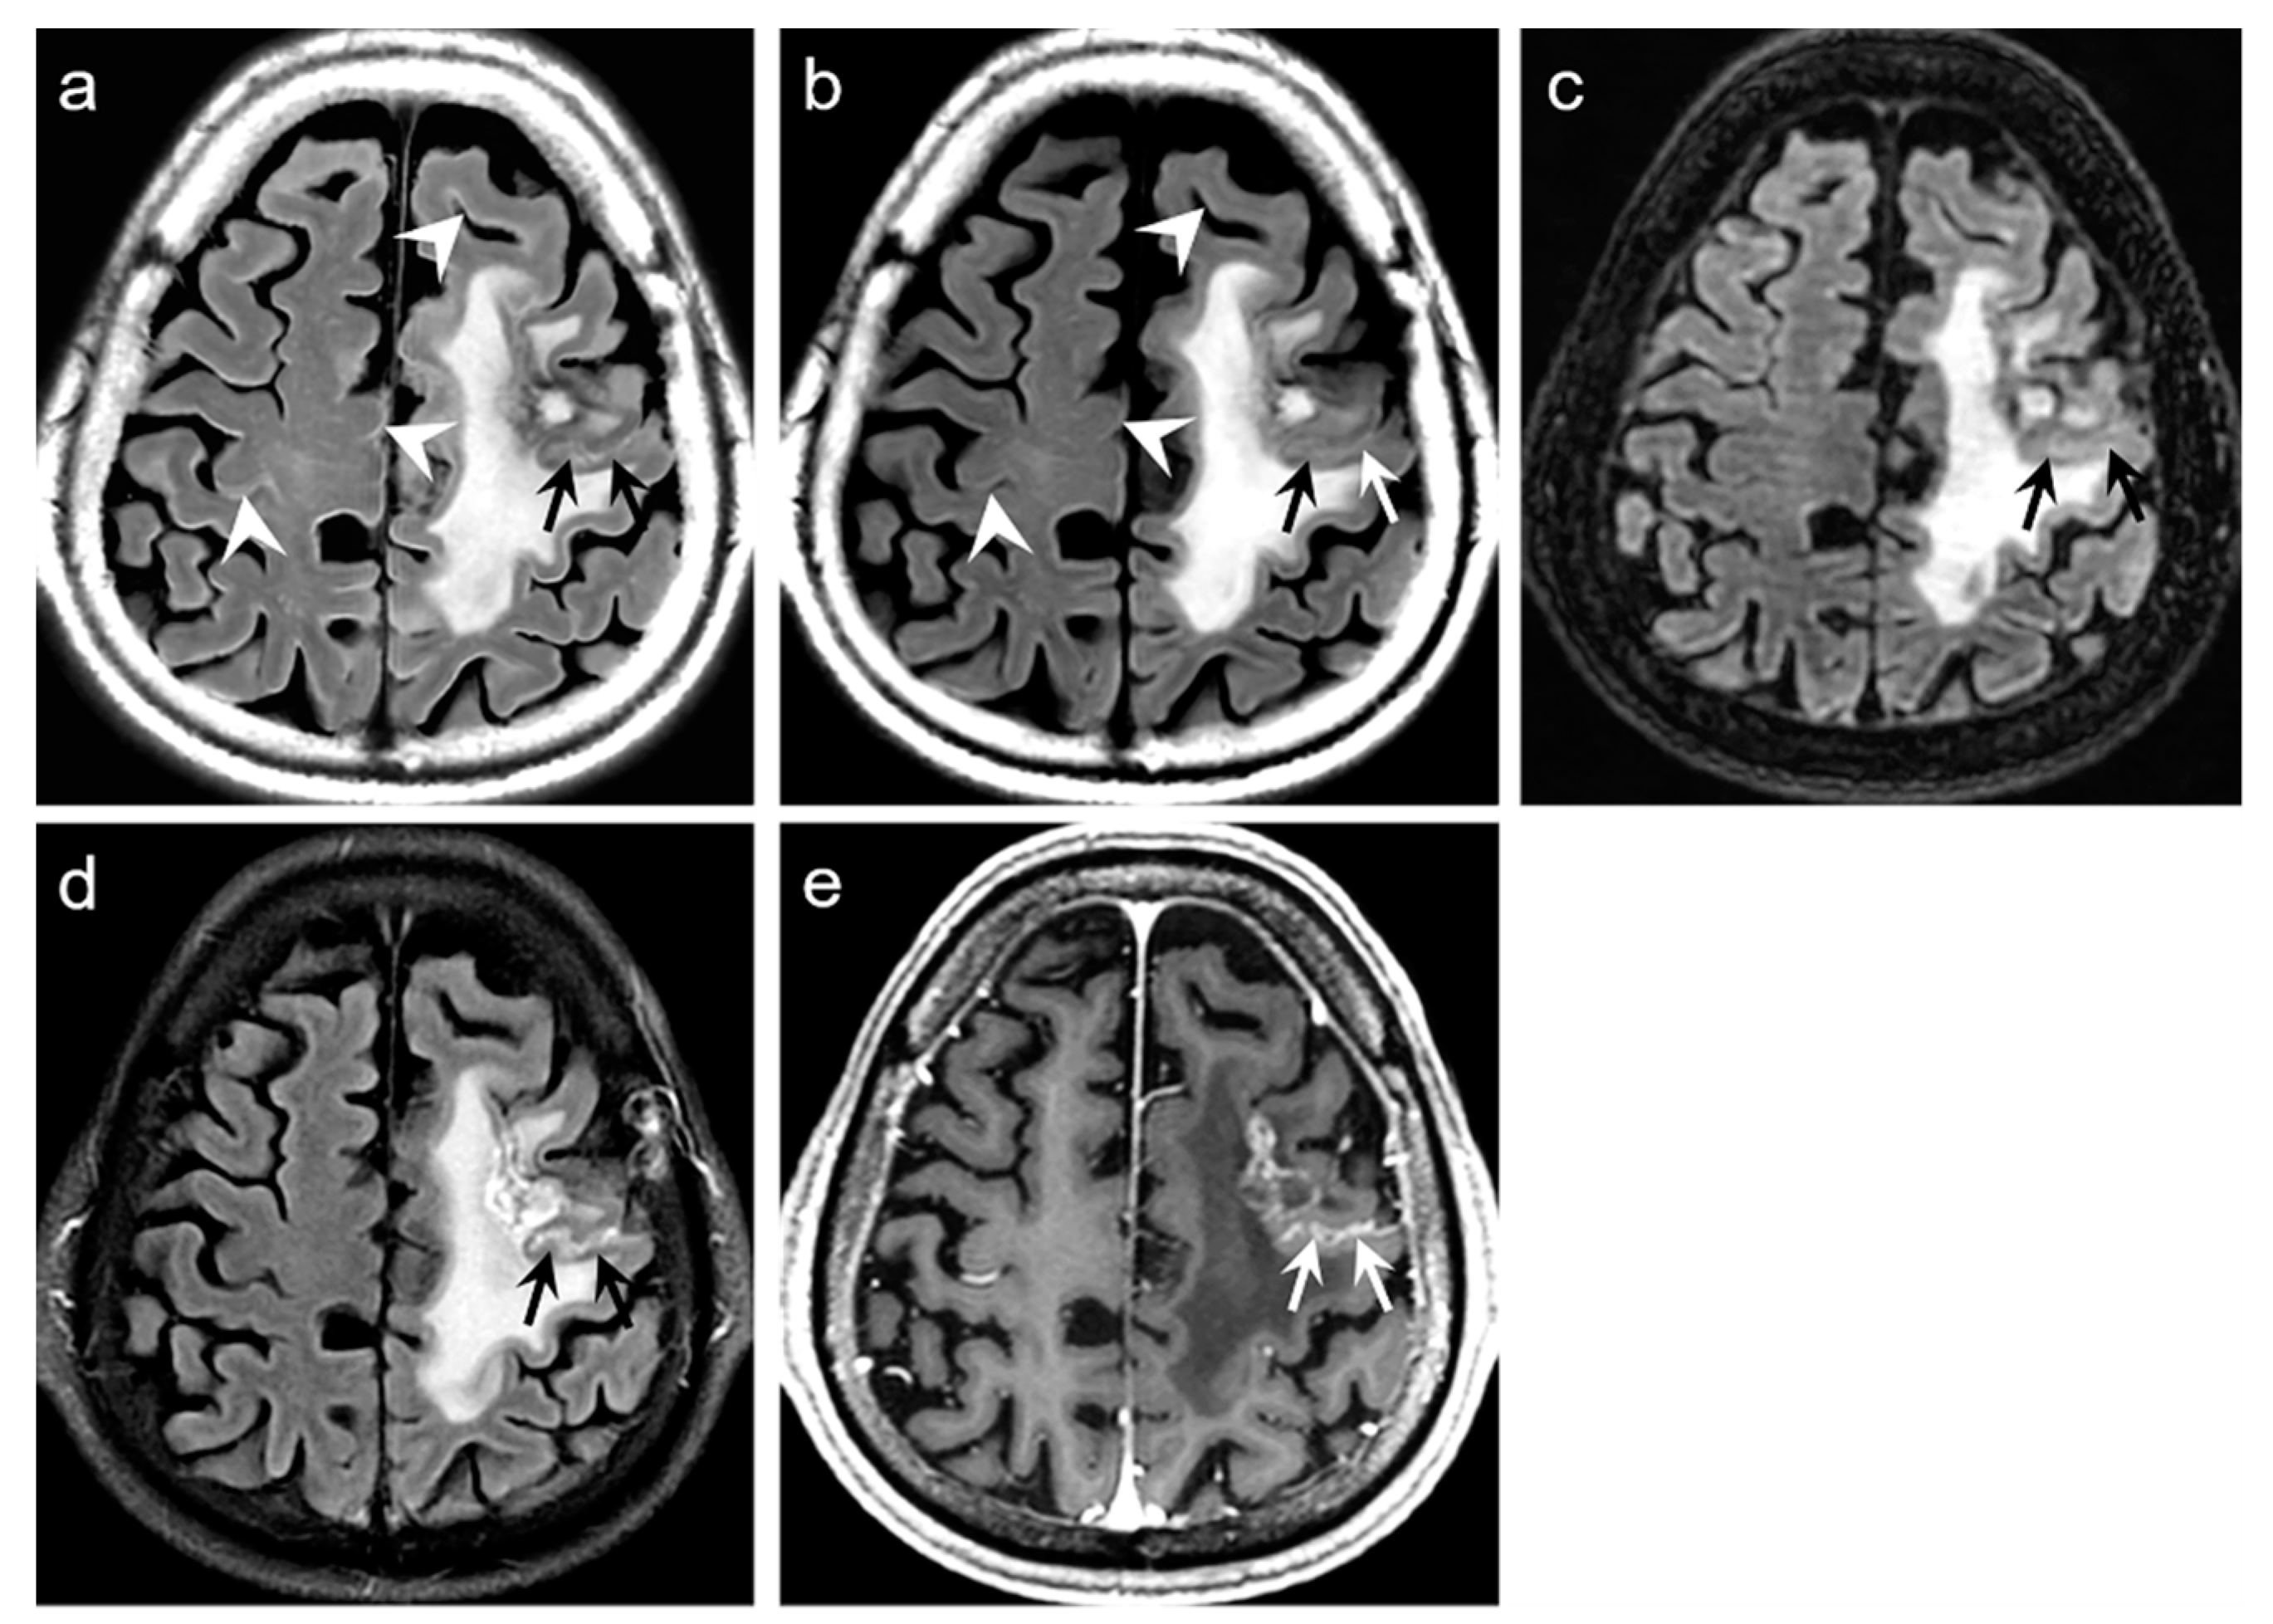

Representative examples are depicted in

Figure 2,

Figure 3,

Figure 4 and

Figure 5.

p < 0.0001). The average mean scores of the degree of preserving the preexisting periventricular WM hyperintensities or lesion conspicuity were not statistically significant for DL-FLAIR and native synthetic FLAIR: 4.69 ± 0.68 vs. 4.70 ± 0.61 (

p = 0.217). Among the 319 patients, there was no case of generation of artificial pseudolesions during DL processing. However, it was possible to identify incomplete preservation of the preexisting true hyperintensities on DL-FLAIR images in 11 patients (3.4%) among 319 patients owing to the unexpected partial removal of the true hyperintensities (

Figure 3b and

Figure 4b). The mean scores of the typical synthetic FLAIR artifacts including surface hyperintensities, granularities, or cortical swelling were identified for DL-FLAIR and native synthetic FLAIR images as follows: 1.32 ± 0.51 vs. 3.35 ± 0.68 (

p < 0.0001) (

Figure 2). In addition, other artifacts that substantially degraded the image quality, such as flow artifacts, were also improved in DL-FLAIR rather than in the native synthetic FLAIR: 1.27 ± 0.46 vs. 2.43 ± 0.72 (

p < 0.0001) (

Figure 2d).

In terms of image artifacts, the typical synthetic FLAIR artifacts were significantly improved in DL-FLAIR images (

Figure 2), which is consistent with the original work [

In the present study, we could identify the incomplete preservation of pre-existing true hyperintensities on DL-FLAIR images in 11 patients, owing to the unexpected partial removal of the true hyperintensities. In all these cases, the hyperintense lesions were located in the vicinity of cystic encephalomalacias, and the lesions were considered to be reactive gliosis. The reason for this finding is unclear; however, it may be related to the processing of DL-based artifact correction to distinguish artifacts from true hyperintensities, especially when the true hyperintensities were seen near fluid-containing lesions, making the fluid-lesion interface likely to be similar to the CSF-brain parenchyma interface. We believe that the issue can be solved if the DL algorithm is improved through a further training process using various pathologic cases that can differentiate a normal CSF-tissue interface from the lesion-fluid interface.